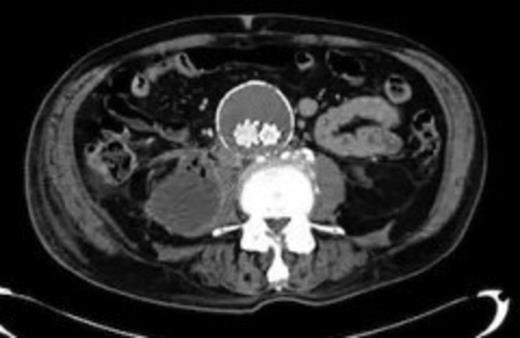

An 82 year old gentleman with known peripheral vascular disease and previous open popliteal aneurysm repair underwent endovascular repair of a 58mm infrarenal abdominal aortic aneurysm (Fig. 1) using a Cook Zenith bifurcated prosthesis The Zenith Flex® AAA Endovascular Graft (Cook Medical Inc., Bloomington, USA). The operation, which was performed under general anaesthetic and bilateral groin cut downs with intravenous prophylactic antibiotic cover on induction (Co-amoxiclav 1.2g) was uneventful. The main body was deployed via the right side. Completion angiograms showed satisfactory exclusion of the aneurysm sac with good graft position and no endoleaks. Post operatively the patient had a brief period of low grade pyrexia and lower abdominal pain that settled spontaneously. This was thought to be due to post implant graft reaction. Pre-discharge imaging with plain abdominal X-rays was deemed satisfactory.